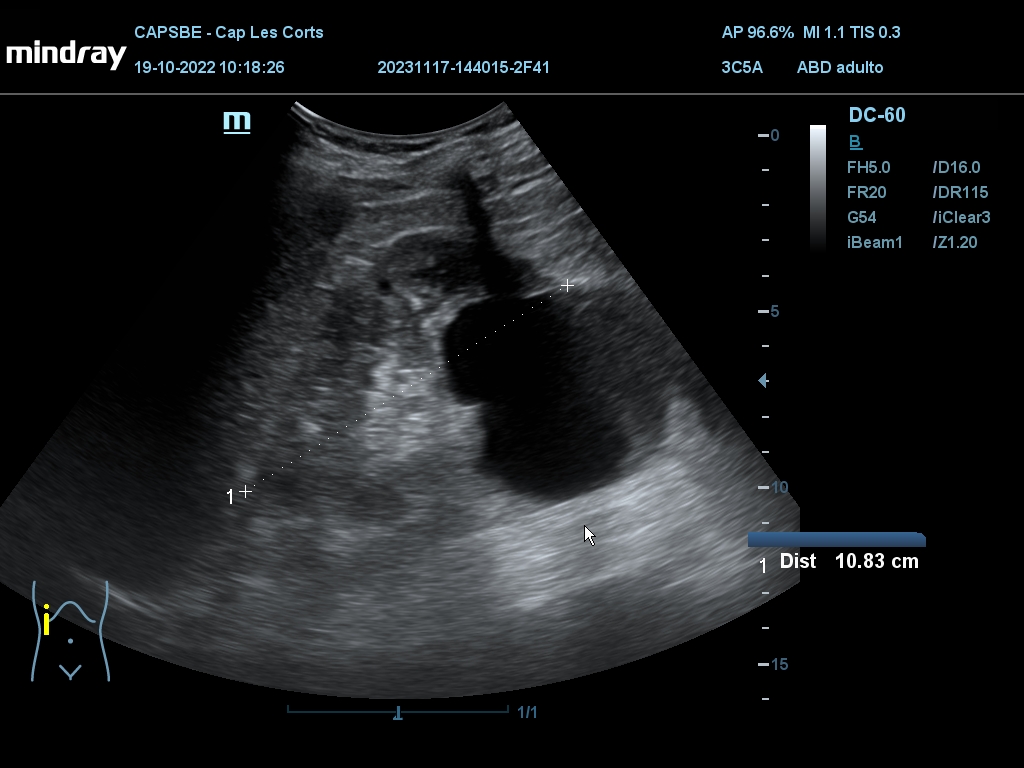

Hallazgos ecográficos

Derrame pericárdico. Vesícula biliar con grosor parietal de 1,6 cm, heterogénea, no se moviliza con cambios posturales. Quistes renales derechos, mayor de 7 cm. Aorta ateromatosa y aneurismática de 36 x 42 mm. Sin líquido intraabdominal.

(Se adjuntan imágenes del derrame, engrosamiento biliar, riñón derecho y aneurisma de aorta).